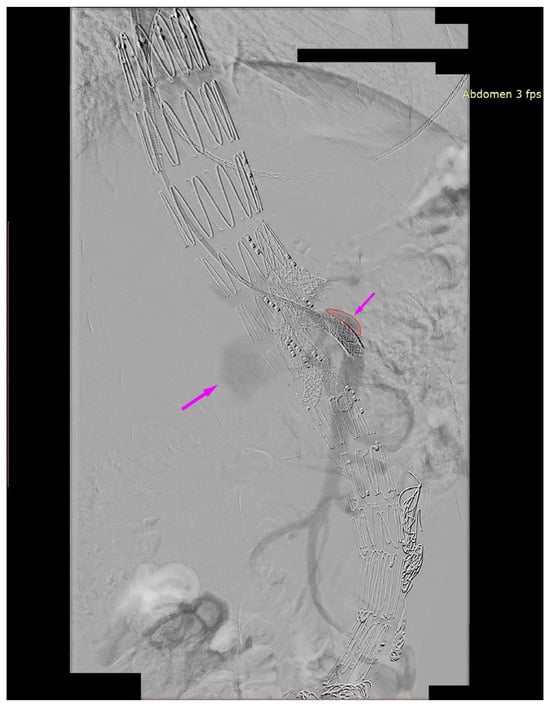

We present the case of an 82-year-old male patient who appeared in the emergency department due to progressive weakness and abdominal pain (2024). Due to a drop in blood pressure to 80/40 mmHg, a continuous infusion of norepinephrine was initiated. The hemoglobin level was approximately 5.1 g/dL. His medical history included generalized atherosclerosis, renal failure, and a thoracoabdominal aortic aneurysm (TAAA) treated with endovascular aneurysm repair (EVAR) using stent-graft implantation 4 years earlier (2020). At that time, the angio-CT scan revealed an aneurysm starting just below the celiac trunk, extending to the superior mesenteric artery (SMA) and both renal arteries (RAs). The maximum diameter of the aortic aneurysm was 51 mm; however, the left common iliac artery measured 41 mm in diameter, an indication for thoracoabdominal stent graft implantation. The aortic aneurysm itself was completely free of mural thrombus. The patient had also experienced a heart attack 16 years earlier and a transient ischemic attack (TIA) 2 years earlier. Following the stent graft implantation, he underwent multiple successful interventions to address endoleaks. One year after implantation, endovascular treatment with embolization coils was performed to eliminate leakage from the lumbar artery (LA) (2021). Three years post-implantation, he was admitted to address leakage from the inferior mesenteric artery (IMA) using embolization coils as well (Figure 1) (2023). In 2024, an X-ray and CT scan revealed a rupture in a branch of the stent graft located in the SMA in its middle part, along with an enlarged aneurysm sac (74 mm) due to the fracture and leakage (Figure 2, Figure 3, Figure 4 and Figure 5). The angio-CT scan did not reveal any contrast extravasation beyond the vessel wall. However, significant contrast leakage was visible in the area of the visceral arteries within the aneurysm sac. The implanted device was the Zenith t-Branch Thoracoabdominal Endovascular Graft, and the ruptured branch was identified as the Bentley BeGraft (Bentley InnoMed GmbH, Hechingen, Germany). Urgent surgical intervention was performed. Intraoperative angiography (IA) showed a breach in the continuity of the BeGraft material within the SMA, with contrast leakage into the aneurysm sac (Figure 6 and Figure 7). To address the leakage and restore the continuity of the SMA branch, an additional BeGraft Plus 8 × 57 mm was implanted into the damaged branch. Subsequent IA and control CT scans confirmed the elimination of leakage, restoration of stent graft continuity, and revascularization of the SMA (Figure 8, Figure 9 and Figure 10). The surgery was completed without complications, and the patient was discharged home in good general condition. The patient returned for follow-up 3 weeks after the last intervention. An angio-CT examination was performed, revealing no enlargement of the aneurysm sac (74 mm), confirming the elimination of the endoleak, and demonstrating successful revascularization of the SMA. Ongoing follow-up will be continued.

Figure 7. Ruptured superior mesenteric artery branch of stent graft. Leakage outside the stent graft after administration of contrast to the SMA branch. Visible leakage into the aneurysm sac. The leakage is marked with arrows. Intraoperative angiography.

Figure 8. Successful SMA revascularization after BeGraft implantation. No visible contrast leakage. Intraoperative angiography.